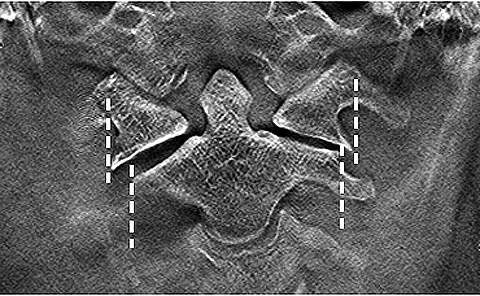

Case 3 – 58-year-old female: a patient who had fallen down stairs at home was immediately hospitalized after CT confirmed a Jefferson fracture. The treatment for a Jefferson fracture is determined according to whether the transverse ligament is intact or broken. This is evaluated from the degree of lateral dislocation of the lateral mass of the atlas with respect to the lateral mass of the axis on both sides³. Frontal tomosynthesis of the cervical vertebrae was performed the day after hospitalization. It provided better evaluation of the lateral mass of the atlas and axis than general radiographs or CT (Fig. 12). Conservative treatment by Halo vest fixation was performed.